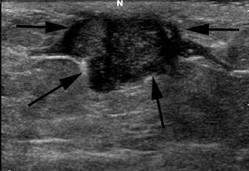

- Siêu âm tuyến vú:

Siêu âm tuyến vú trái: Hình ảnh tổ chức giảm âm dưới quầng vú trái, kích thước 5x5,4cm